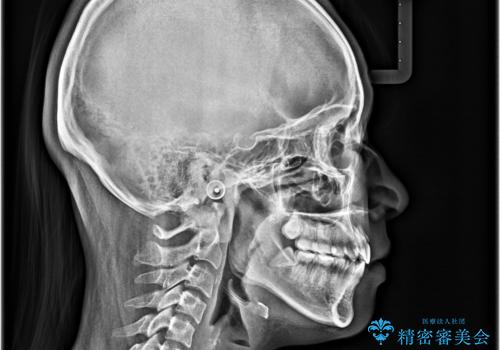

横顔の印象を変えたい ワイヤー装置での抜歯矯正

- 口元の突出感と上下前歯のズレを気にして来院された患者様です。

舌の突出癖により上下の前歯は非接触となっている状態でした。

舌のトレーニングを行わないと上下前歯の接触達成は困難であるため、トレーニングをしっかりと行っていただきながら、治療を進めて行くこととしました。

突出感改善のため、上下左右の第一小臼歯4本を抜歯し、ワイヤー装置にて矯正治療を行うこととしました。

舌のトレーニングをしっかりと行ってくださり、予定通りの期間で理想的な仕上がりを達成することができました。